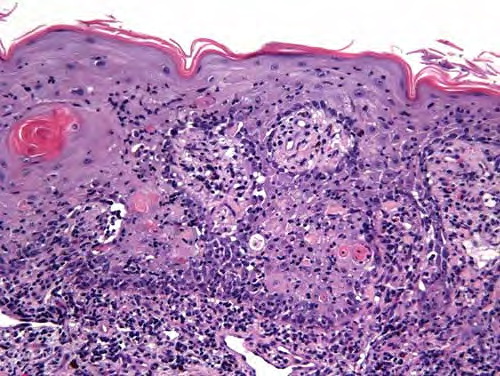

Atlas of skin histopathology

Paraneoplastic pemphigus = الفقاع نظير السرطاني